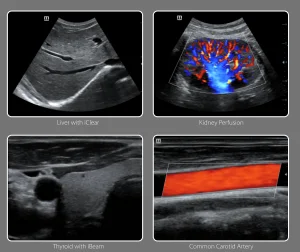

iClear

Clear speckle-reduction imaging technology reduces the image

speckle noise and acquires clearer and sharper lesion contours.

iBeam

iBeam spatial-compounding imaging technology permits use of multiple transmitting angles to form a single image, resultina in enhanced contrast resolution,ana improvea visuauzation.

Auto IMT

Auto IMT (Intima Media Thickness) automatically detects and calculates the thickness of carotid intima-media. With a comprehensive IMT report, auto IMT facilitates an accurate and efficient assessment of carotid condition.